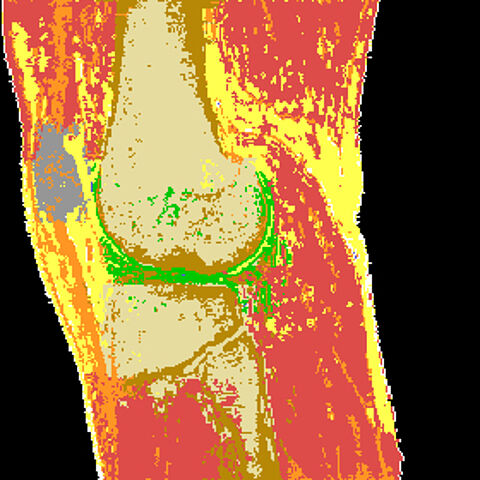

Wissenserwerb (WE)AUDIGON soll insbesondere Frühschäden des Gelenkknorpels des Kniegelenks erkennen und quantifizieren helfen. Damit soll es einerseits als Hilfsmittel in der medizinischen Grundlagenforschung, andererseits als Tool zur Beurteilung von Behandlungsversuchen genutzt werden. Grundlage sind kernspintomographische 3D-Bildsequenzen.